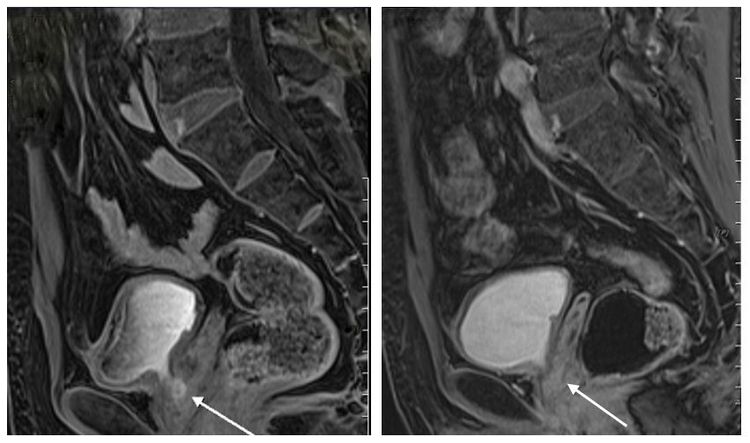

老醫師因頻尿、解不乾淨發現攝護腺癌(左),經過37次光子刀放射線治療讓腫瘤消失 (右)。中港澄清醫院提供

沒想到追蹤一年半後,老醫師今年中再次回診檢查,腫瘤指數已經升到7.1,超過正常指數4,核磁共振發現攝護腺癌已從原本的0.5公分長大約0.9公分,經與醫師討論,決定採用不開刀的光子刀放射線治療,歷經每天1次、共計37次光子刀放射線治療後,腫瘤指數也掉到0.76,攝護腺癌也已完全消失。